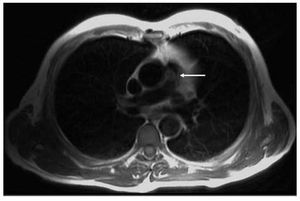

The patient came to the emergency room with a persistent fever of 20 days' duration, associated over the past 5 days with dyspnea and fatigue on minimum minimal exertion. He was admitted to the cardiology department; serial blood cultures isolated Streptococcus viridans. Transesophageal echocardiography showed a mildly dysfunctional dilated right ventricle, with a round, slightly mobile image on the pulmonary trunk (homograft), indicative of an endocarditis vegetation that considerably increased the pre-existing stenosis (Figure 1A); the maximum transpulmonary gradient was 125 mm Hg (Figure 1B). Magnetic resonance imaging was performed to provide better anatomic definition and tissue characterization of the homograft and lesion (Figure 2, arrow).

Figure 2.